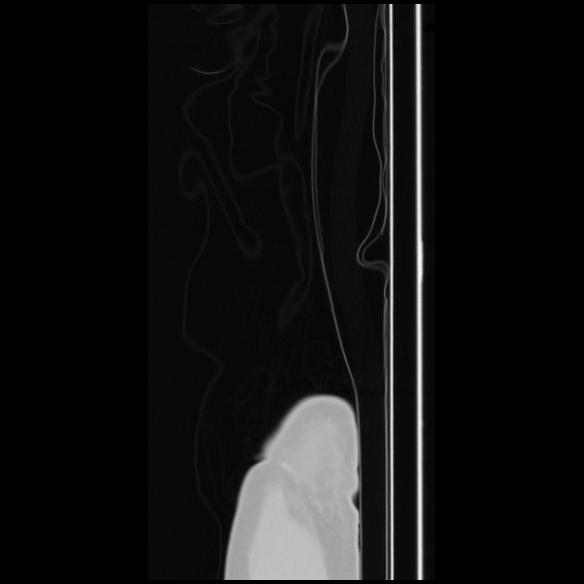

7 CUERPO,CE,Sagittal,3.000,CUERPO,Sagittal,